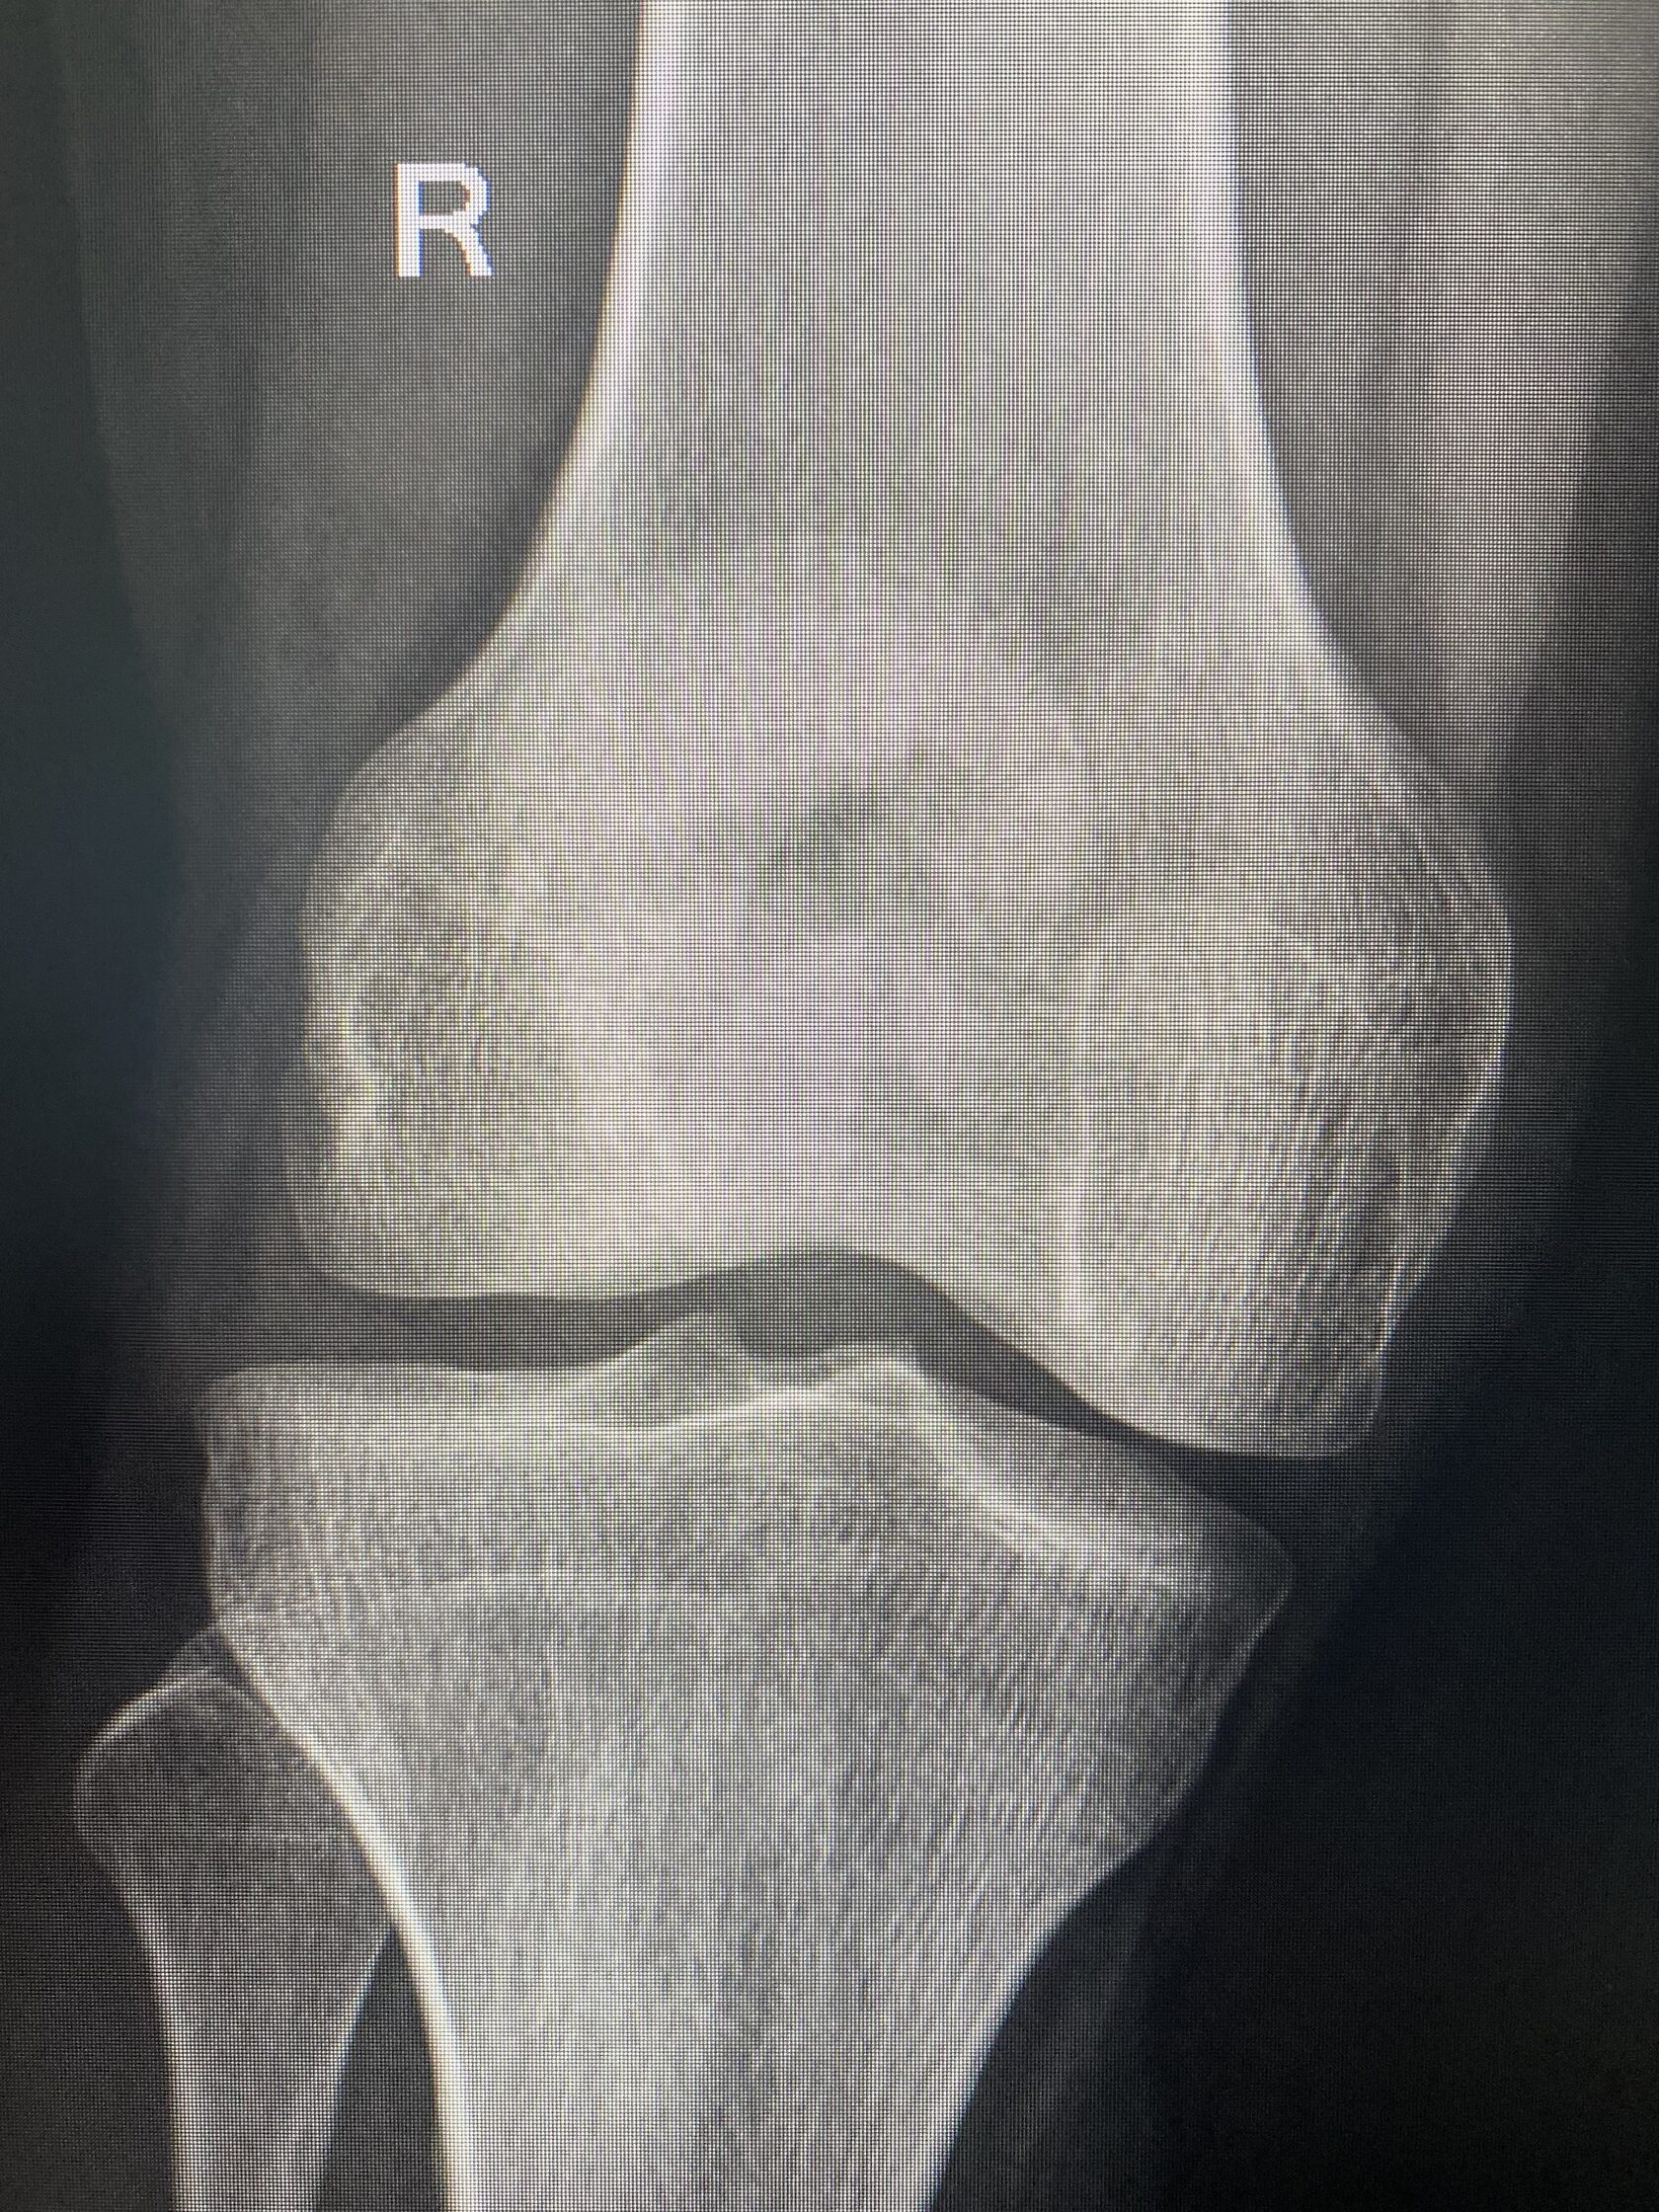

- Рентгенография колена: оценка степени артроза и костных изменений.